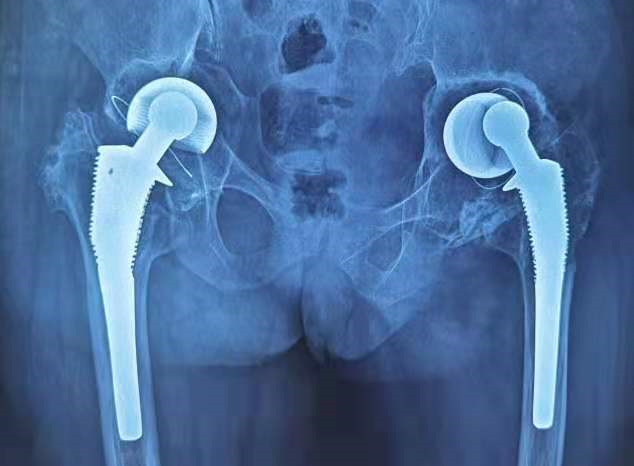

术前X线: